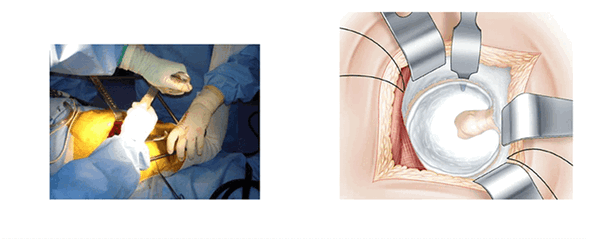

Начало операции, разрез поверхности. (L’abord superficiel)

Голеностопный сустав помещается на опоре. Колено согнуто и повернуто вовнутрь. Поверхность кожи обрабатывают антисептиком и делают разрез. В разрезе видна большая ягодичная мышца. Таким образом открывают операционное поле. Большая ягодичная мышца рассекается атравматическим способом снизу вверх по направлению волокон. В нижней части разреза рассечение широкой фасции облегчает манипуляции. В рану вводится рамка Шарнли. Она будет держать края большой ягодичной мышцы в течении всей операции. Передний клапан рамки располагается по направлению большого вертела.

Рассечение суставной сумки. (La section capsulaire)

Суставную сумку открывают Т-образным разрезом. Разрез начинают с заднебокового края вертлужной впадины, рядом с грушевидной мышцей. Разрез проходит по оси шейки бедра от зада к переду холодным скальпелем вблизи от седалищного нерва. Далее разрез продолжают в направлении перпендикулярном большому вертелу. Края раздвигают проволочными ретракторами.